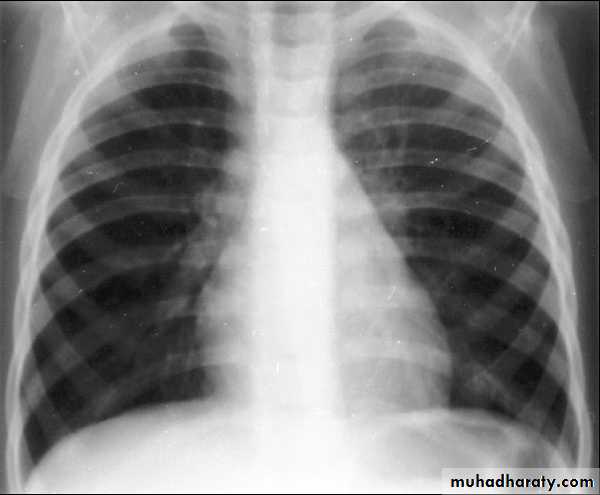

Q 10/ A previously healthy 2-year-old black child has developed a chronic cough during the previous 6 weeks. He has been seen in different emergency rooms on two occasions during this period and has been placed on antibiotics for pneumonia. Upon auscultation, you hear normal breath sounds on the left. On the right side, you hear decreased air movement during inspiration but none upon expiration. Inspiratory (A) and expiratory (B) radiographs of the chest are shown below. Which of the following is the most appropriate next step in making the diagnosis in this patient?

A

B

Recurrent pneumonias in an otherwise healthy child should suggest the potential for anatomic blockage of an airway. In the patient in this question, the findings on clinical examination suggest a foreign body in the airway. Inspiratory and expiratory films can be helpful. Routine inspiratory films are likely to appear normal or near normal (as outlined in the question and noted in the first radiograph). Expiratory films will identify air trapping behind the foreign body (as noted on the second radiograph). It is uncommon for the foreign body to be visible on the plain radiograph; a high index of suspicion is necessary to make the diagnosis. Suspected foreign bodies in the airway are potentially diagnosed with fluoroscopy, but rigid bronchoscopy is not only diagnostic but also the treatment of choice for removal of the foreign body.